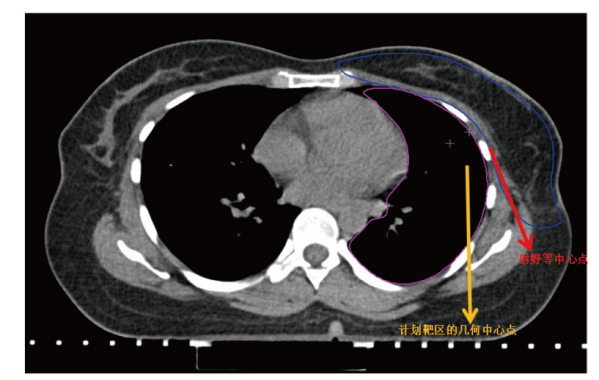

基于内缘切线野的调强放疗与容积弧形调强放疗在左侧乳腺癌保乳术后放疗中的剂量学研究

Dosimetric study of intensity-modulated radiotherapy and volumetric intensity modulated arc therapy based on the inner edge tangent field for radiotherapy after breast-conserving surgery of left-sided breast cancer

目的 探究左侧乳腺癌保乳术后基于内缘切线野(IETF)的调强放疗(IMRT)与容积弧形调强放疗(VMAT)的剂量学差异。方法 选取2022年6月至2023年6月收治于云南省肿瘤医院放射治疗科的35例左侧乳腺癌保乳术后行IMRT患者的定位CT和靶区危及器官(OAR)等资料,针对同一患者分别设计基于IETF的IMRT和VMAT两种放疗计划,IETF-IMRT和IETF-VMAT;对两种放疗计划的靶区和OAR剂量及计划执行时间进行比较。结果 靶区剂量:IETF-IMRT和IETF-VMAT两种放疗计划靶区的D98%分别为(47.92±0.51)、(48.21±0.33)Gy,D50%分别为(52.04±0.22)、(51.91±0.26)Gy,D2%分别为(53.93±0.36)、(53.62±0.41)Gy,适形指数分别为0.84±0.03、0.87±0.02,均匀性指数分别为0.12±0.01、0.10±0.01,差异均有统计学意义(t=-3.87,P<0.001;t=3.53,P=0.001;t=5.30,P<0.001;t=-13.60,P<0.001;t=6.24,P<0.001)。OAR剂量:IETF-IMRT和IETF-VMAT两种放疗计划左肺V5分别为(31.91±6.28)%、(33.99±6.31)%,V20分别为(11.71±2.06)%、(9.73±2.12)%,差异均有统计学意义(t=-4.18,P<0.001;t=12.40,P<0.001);右肺V5分别为(0.11±0.08)%、(7.13±3.12)%,Dmean分别为(1.05±0.12)、(2.71±0.27)Gy,差异均有统计学意义(t=-33.62,P<0.001;t=-13.30,P<0.001);脊髓D2%分别为(1.08±0.11)、(4.83±1.40)Gy,差异有统计学意义(t=-15.99,P<0.001)。左肺Dmean分别为(7.45±1.08)、(7.37±1.03)Gy,心脏Dmean分别为(4.21±0.96)、(4.41±0.48)Gy,右侧乳腺Dmean分别为(3.74±1.52)、(3.48±1.11)Gy,差异均无统计学意义(t=1.16,P=0.253;t=-1.76,P=0.088;t=1.41,P=0.169)。计划执行时间:IETF-IMRT和IETF-VMAT两种放疗计划执行时间分别为(10.73±1.21)、(2.18±0.17)min,差异有统计学意义(t=44.71,P<0.001)。结论 IETF-IMRT和IETF-VMAT均能满足临床要求,但两种技术各有特点。靶区适形性和均匀性方面,IETF-VMAT略优;两种计划的OAR剂量均显著低于乳腺癌术后放疗剂量限值,其中,IETF-IMRT计划的左肺V5,右肺V5、Dmean和脊髓D2%略低,IETF-VMAT计划的左肺V20略低。IETF-VMAT较IETF-IMRT显著缩短了计划执行时间,可极大地降低患者体位变化引起的剂量偏差,明显提高患者放疗体验感和舒适度;综合考虑,左侧乳腺癌保乳术后放疗IETF-VMAT较IETF-IMRT更具优势。

Objective To explore the dosimetry difference between intensity-modulated radiotherapy (IMRT) and volumetric intensity modulated arc therapy (VMAT) based on the inner edge tangent field (IETF) after left-sided breast conserving surgery. Methods The localization CT and target organ at risk (OAR) data of 35 patients with left-sided breast cancer treated with IMRT after breast conserving surgery at Department of Radiotherapy in Yunnan Cancer Hospital from June 2022 to June 2023 were selected. The IETF-IMRT and the IETF-VMAT plans were designed for the same patient based on IETF, the dosimetry differences of target areas and OAR, as well as the planned execution time were compared between the two groups. Results Dosimetry of target areas: for IETF-IMRT and IETF-VMAT, the D98% of the planning target volume were (47.92±0.51) and (48.21±0.33) Gy, respectively, while the D50% were (52.04±0.22) and (51.91±0.26) Gy, respectively, and the D2% were (53.93±0.36) and (53.62±0.41) Gy, respectively, the conformity index were 0.84±0.03 and 0.87±0.02, respectively, while the homogeneity index were 0.12±0.01 and 0.10±0.01, respectively, with statistically significant differences (t=-3.87, P<0.001; t=3.53, P=0.001; t=5.30, P<0.001; t=-13.60, P<0.001; t=6.24, P<0.001). Dosimetry of OAR: for IETF-IMRT and IETF-VMAT, the left lung V5 were (31.91±6.28)% and (33.99±6.31)%, respectively, and the V20 were (11.71±2.06)% and (9.73±2.12)%, respectively, with statistically significant differences (t=-4.18, P<0.001; t=12.40, P<0.001). The right lung V5 were (0.11±0.08)% and (7.13±3.12)%, respectively, and the Dmean were (1.05±0.12) and (2.71±0.27) Gy, respectively, with statistically significant differences (t=-33.62, P<0.001; t=-13.30, P<0.001). The spinal cord D2% were (1.08±0.11) and (4.83±1.40) Gy, respectively, with a statistically significant difference (t=-15.99, P<0.001). The left lung Dmean were (7.45±1.08) and (7.37±1.03) Gy, the heart Dmean were (4.21±0.96) and (4.41±0.48) Gy, and the right-sided breast Dmean were (3.74±1.52) and (3.48±1.11) Gy, respectively, with no statistically significant difference (t=1.16, P=0.253; t=-1.76, P=0.088; t=1.41, P=0.169). Planned execution time: the execution time of IETF-IMRT and IETF-VMAT was (10.73±1.21) and (2.18±0.17) min, respectively, with a statistically significant difference (t=44.71, P<0.001). Conclusion Both IETF-IMRT and IETF-VMAT can meet clinical requirements, however the two techniques have their own characteristics. IETF-VMAT has better conformity and homogeneity of target region. The planned OAR dosimetry in both plans are significantly lower than the dose limit of postoperative radiotherapy for breast cancer, among which the left lung V5, the right lung V5, Dmean and spinal cord D2% of IETF-IMRT are slightly lower, the left lung V20 of IETF-VMAT is slightly lower. IETF-VMAT significantly reduces the planned execution time compared with IETF-IMRT, thus can greatly reduce the dose deviation caused by patient position change, and significantly improve patients experience and comfort of radiotherapy. Taken together, IETF-VMAT has advantages over IETF-IMRT in radiotherapy after breast conserving surgery of left-sided breast cancer.